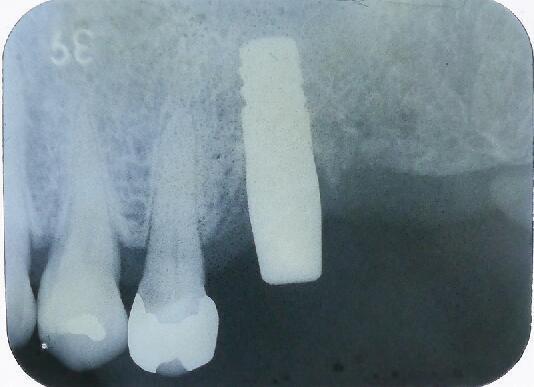

オペ当日のエックス線写真です

4ヵ月後のエックス線写真です すでに骨が出来ております

その部位の拡大エックス線像です 上顎には他の場所と違い上顎洞という頭を軽くするための空洞があり骨が2~4ミリ程度しかなく、インプラントは大変困難です。

前方から見たエックス線像

当院では最新のHAコーティングタイプのインプラント体(フィクスチャー)を使い一回の手術でスーパーソケットリフト術で行います。埋入後4ヶ月で最終のかぶせ物をして完成となります。

大変シンプルで患者さんの負担も最小限ですみます。